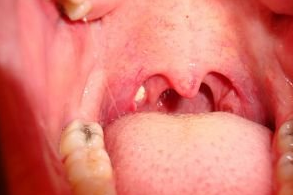

Bademcik taşı (Tonsillolith); bademcik ceplerinde görülen sarı/beyaz renkte, kötü kokulu partiküllerdir. Bademcikler düzensiz yüzeyli pürüzlü organlardır. Üzerlerinde çok sayıda Crypts adında çukurlar ve boşluklar bulunur. Dökülen mukoza hücreleri, yemek parçaları ve bademcik iltihabi kalıntıları tükürükle yutulurken bazı şanssız kişilerde bademciklerdeki çukurlarda birikip topaklaşarak kitle haline gelir (Resim 1). Ölü hücrelerden oluşan bu kitle bakteriler için mükemmel bir besindir. Ağız içinde koloniler halinde yaşayan değişik türlerde bakteriler olduğunu bildiğimize göre kokunun nereden geldiğini anlamakta zor olmayacaktır.